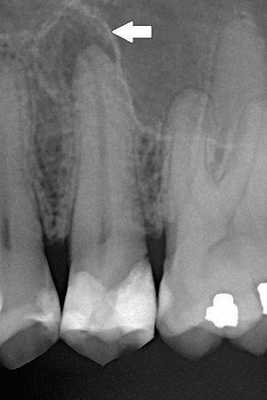

При пародонтозе изменения затрагивают невидимую для глаз человека часть — костную ткань челюсти. Изменения, которые происходят в ней, приводят к подвижности зубов и как результат — их удалению. На уровне кости изменения затрагивают процесс образования костной ткани: новая ткань на фоне разрушения не успевает восстановиться с помощью специальных клеток, строящих ее. Ткань кости челюсти постепенно убывает. Этот процесс виден только на рентгенограмме челюстей. [5]

Для легкой степени тяжести характерно отсутствие жалоб, изменения в костной ткани видны только на рентгеновском снимке.

Средняя степень пародонтоза характеризуется оголением шеек зубов и корней (до 3мм), на рентгеновском снимке можно заметить снижение высоты костных перегородок между зубами, достигающее половины высоты корней зубов. Пациенты могут жаловаться на появление неприятных ощущений в деснах, зуда, на изменение положения зубов (наклон, смещение в виде веера).

При тяжелой степени пародонтоза оголение шеек зубов и корней доходит до 5 мм, костные перегородки разрушены уже на 2/3 длины корней зубов, что приводит к появлению подвижности зубов и изменению их положения в челюсти и смыкания между собой.

Степень разрушения кости челюстей исследуют с помощью рентгенологического исследования (панорамная рентгенография, компьютерная томография), по которой можно различить стадии пародонтоза. Плотность костной ткани изучают с помощью эхоостеометрии. Изучение состава слюны и микрофлоры полости рта дает большие возможности в терапии пародонтоза. [8]